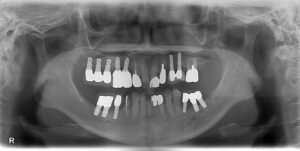

下の前歯の欠損部をインプラントしたいとのことで来院されました。

欠損部はブリッジにて治療されていましたが、両側の支台歯部分に負担がかかり根の先が化膿していたため、神経の治療も必要になっていました。

歯を喪失してから、かなりの年月が経っていた為、歯茎のラインがかなり下にあります。

その為、審美的に歯茎まで覆うような被せを入れさせていただきました。